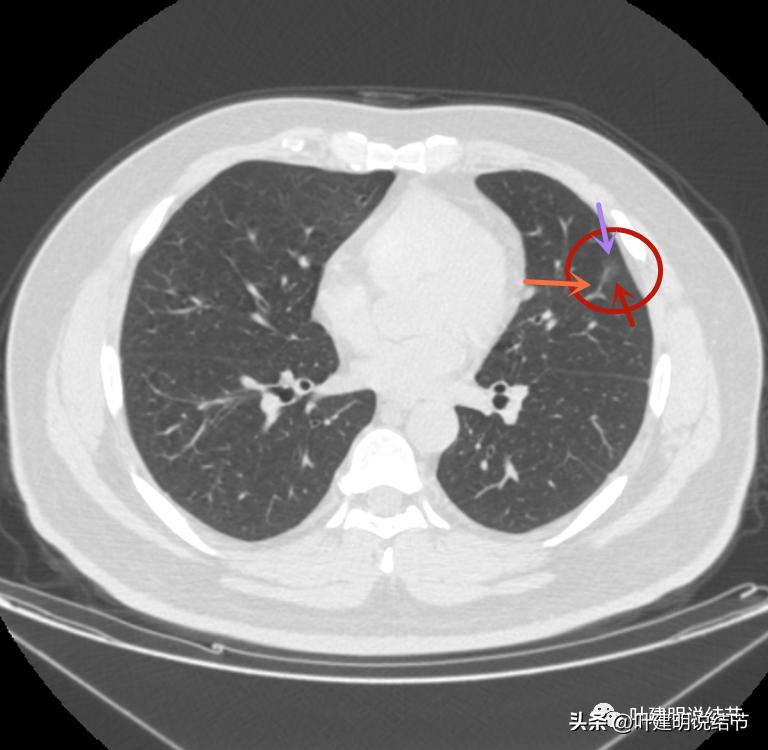

左上病灶2与左上病灶3:

病灶2出现,还只有一点点磨玻璃影,血管走行有点异样

密度略显高,有微血管进入(桔色箭头),边缘略模糊,但轮廓还是较清

中间有实性成分出现(粉色箭头),微血管进入明显(桔色箭头),边上有磨玻璃成分(绿色箭头),整体轮廓清

边上另有病灶出现,即左上病灶3(蓝色箭头)

病灶3也有微血管进入(桔色箭头)

病灶3密度不均,轮廓清,有细毛刺样征(紫色箭头)

毛刺征(紫色箭头),微血管征(桔色箭头),实性点状成分(粉色箭头),整体轮廓较清(红色箭头)